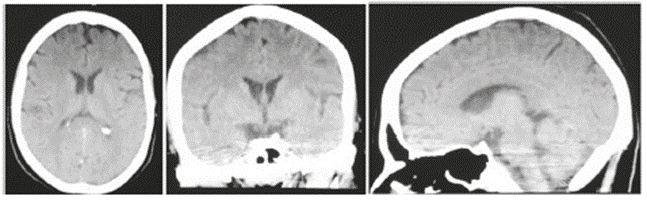

Se realizaron exámenes para descartar organicidad. Una tomografía computarizada (TC) simple de cráneo no evidenció lesiones estructurales (figura). Los estudios paraclínicos séricos mostraban unas adecuadas funciones tiroidea, renal y hepática, equilibrio hidroelectrolítico y hemograma dentro de normalidad (tabla 1), por lo que se descartó cualquier proceso sistémico que pudiera estar asociado con este cuadro.

Figura 1 Tomografía computarizada craneal simple sin evidencia de lesiones intraparenquimatosas. Se considera dentro de los límites normales.